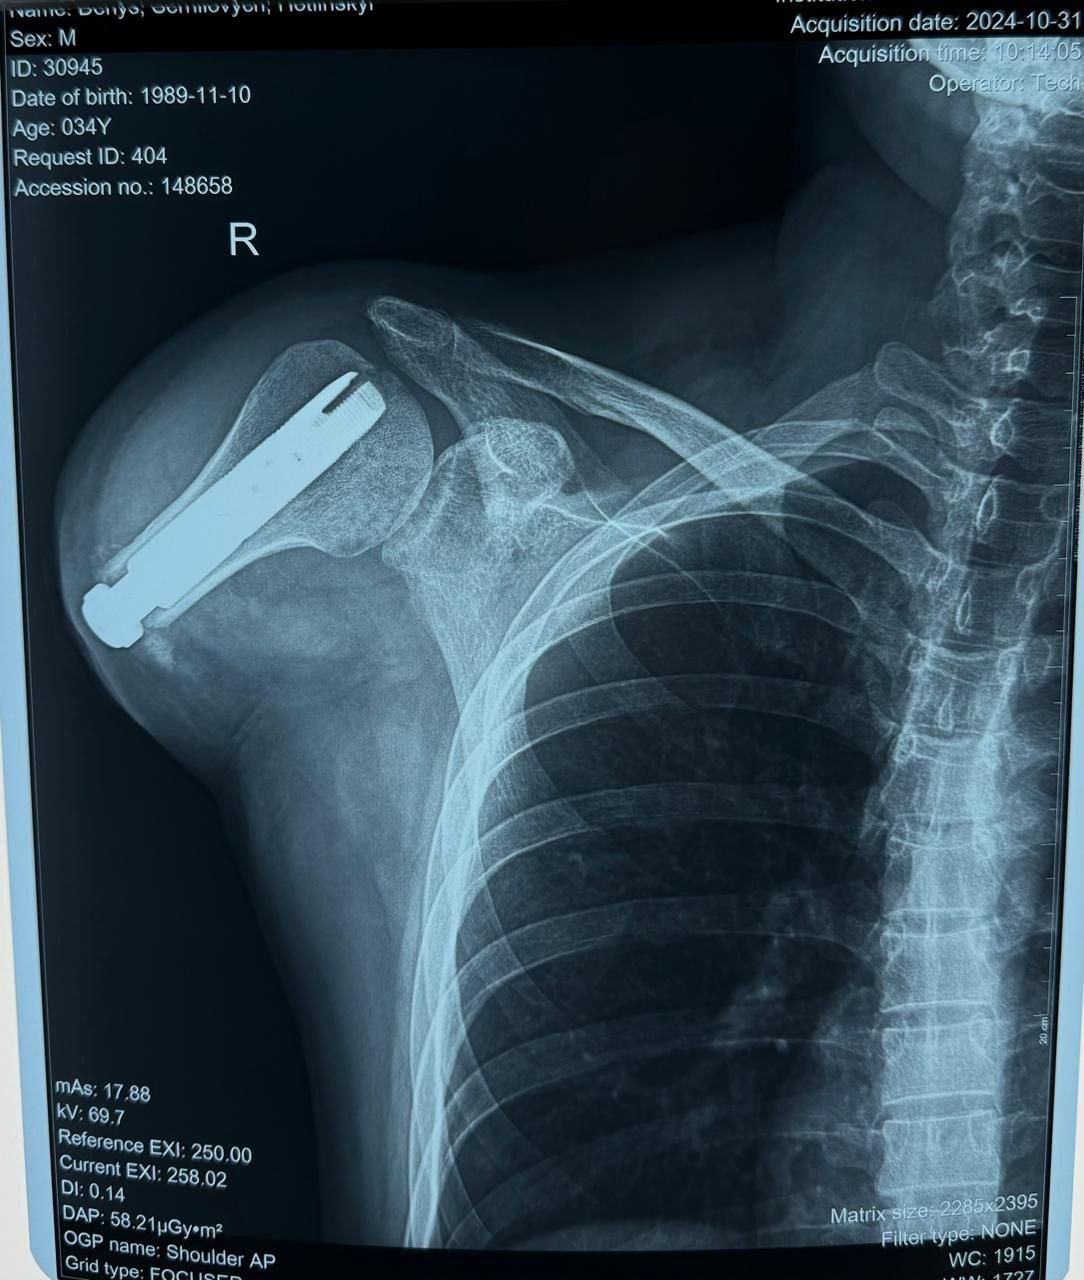

Tytanovi – це сучасний реабілітаційний центр України, який спеціалізується на найскладніших випадках протезування та допомагає постраждалим воїнам відновити себе не тільки фізично, а й морально. Заклад надає допомогу пацієнтам з високими ампутаціями, яким часто відмовляють інші реабілітаційні центри. У рамках співпраці з Respublika Park центр отримує фінансування для проведення високотехнологічних операцій з остеоінтеграції, вартість кожної з яких складає близько 23 000 євро.

“Наш центр працює з найскладнішими випадками ампутацій, часто беручись за ситуації, від яких відмовляються інші реабілітаційні заклади. Завдяки підтримці Respublika Park ми можемо продовжувати надавати високотехнологічну допомогу. Сучасні технології остеоінтеграції дають шанс на повноцінне життя навіть у найскладніших випадках”, – прокоментував засновник центру Tytanovi В’ячеслав Запорожець.